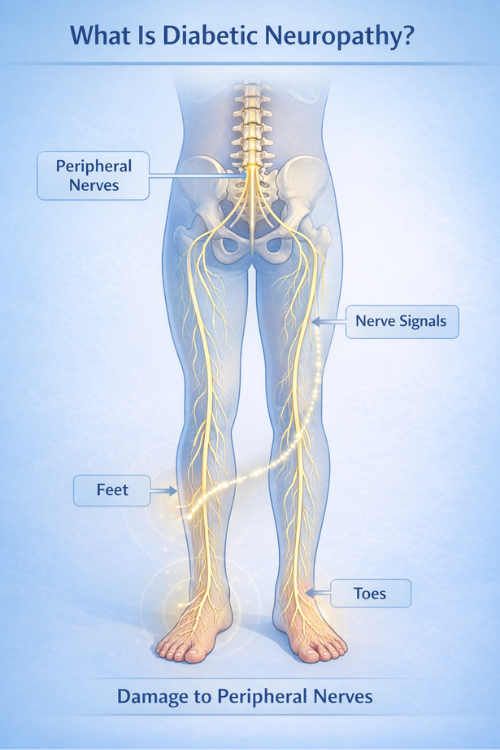

What Is Diabetic Neuropathy?

Diabetic neuropathy refers to nerve damage associated with long-term changes related to diabetes. Nerves carry signals between the brain, spinal cord, and different parts of the body. Because of this role, disruptions in nerve function may therefore influence sensation, movement, and internal regulation throughout the body.

In many situations, diabetic neuropathy primarily affects nerves in the feet and legs first. As a result, early sensory changes may often begin in these areas. As nerve signals gradually change, people may therefore notice numbness, tingling, or reduced sensitivity in these areas.

Over time, nerve changes may influence balance, coordination, or muscle strength. Therefore, understanding diabetic neuropathy can help people better recognize how nerve function may change as metabolic conditions evolve.